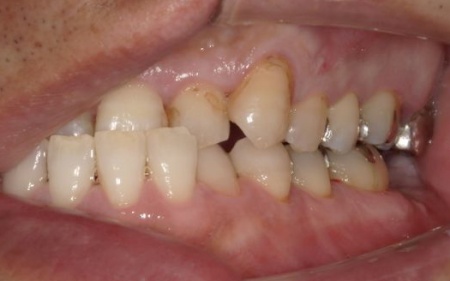

40代男性 虫歯治療やインプラント治療で口腔内全体を修復したあと部分矯正で噛み合わせを改善した症例

拝見したところ、複数の歯に虫歯が見られました。また、過去に治療した詰め物や被せ物が合わなくなっている部分や、歯が欠損している部位もあります。

・右上奥歯

一番奥の歯が欠損し、その手前の歯は詰め物の内部で虫歯が進行しています。

・右上前歯2本

虫歯が認められました。

・右下奥歯3本

噛む面や歯間に虫歯が見られ、歯が欠けている部分もあります。

・左上奥歯

一番奥の歯は、詰め物が合っていませんでした。また、詰め物が外れたままの歯もあります。

・左上前歯2本

虫歯や、被せ物の不具合が見られました。

・左下奥歯

一番奥の歯は虫歯が深くまで進行しており、歯の温存が難しい状態でした。さらに、その手前の歯2本は少し欠けています。

・前歯の噛み合わせ

下前歯が上前歯より前に出ている「反対咬合(こうごう)」で、将来的に歯や顎への負担が生じるリスクがあります。